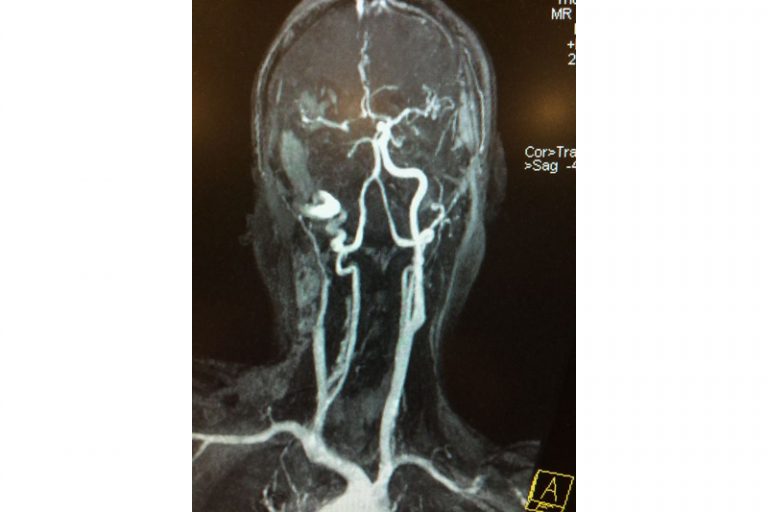

圖:磁力共震造影顯示羅先生右邊頸和腦部血管大動脈全部都被血栓堵塞著。

圖:右邊頸和腦部血管大動脈全部都被血栓堵塞着。

羅先生被送往私家醫院的第一步是進行緊急磁力共振造影,報告顯示羅先生右邊頸和腦部血管大動脈全部都被血栓堵塞着,右邊大腦缺血水腫,導致左邊手腳冇力和神智半昏迷。經過腦血管外科醫生的診斷和急救,在全身麻醉下,醫生使用尤如髪絲微細的導管,經過病人右邊大腿的腹股溝的大動脈而入,導管再經過腹部和胸腔的大動脈一直向上,遊走到病人右邊的頸和腦部血管大動脈,進行機械式血栓吸取內血管治療急救。